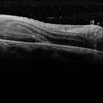

Large Retinal Fold Masking the Optic Nerve

Sep 22 2020 by Sophia El Hamichi, MD

A 69-year-old female, with a history of choroidal melanoma in her left eye with exudative detachment, underwent tumor laser ablation. She then developed a complex combined tractional and rhegmatogenous retinal detachment with a giant retinal tear. The patient underwent surgical repair of her retinal detachment with pars plana vitrectomy and silicone oil. In the post-op, the patient developed large retinal folds masking the optic nerve depicted in the OCT photograph.

Photographer: Belinda Rodriguez, Murray Ocular Oncology and Retina, Miami

Condition/keywords: giant retinal tear, melanoma, pars plana vitrectomy (PPV), retinal fold, silicone oil